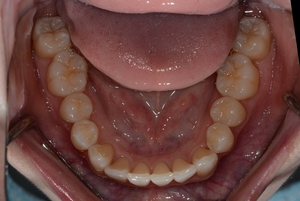

ガタガタとした歯並びや八重歯(叢生)CASE69